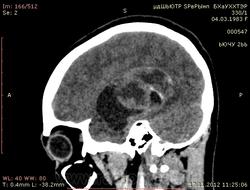

Молодая женщина, 29 лет. Обратилась на прием к неврологу 26.10.12г с  болями в шее, назначено лечение амбулаторно по сосудистой головной боли, остеохондрозу.. После 14.11.12г обратилась к другому неврологу повторно, 16.11.12г направлена в стационар. Жалобы: на снижение зрения, головные боли, головокружения, слабость, повышение температуры. Провели СКТ головного мозга натив и контрастирование. Подскажите пожалуйста, коллеги- Это опухоль? тогда какая (глиобластома, невринома, менингиома?) и локализацию. Спасибо.

Нативное исследование.

Одно можно сказать точно: это не менингиома и не невринома (у тех структура однородная). Это Вам в помощь http://www.radiologyassistant.nl/en/p47f86aa182b3a/brain-tumor-systematic-approach.html

Мне кажется, что тут субэпендимарная глиома. Указываете степень дислокации, накопления и к нейрохирургам.

Согласна с Андреем Юрьевичем. Все остальное возможно, в том числе олигодендроглиома. Впрочем не принципиально. К нейрохирургам!

Только что узнала результаты вскрытия.Гистология пока не готова.

Глиобластома с прорастанием стенки правого бокового желудочка, выраженный отек, смещение срединных структур, вклинение миндалин мозжечка в БЗО.